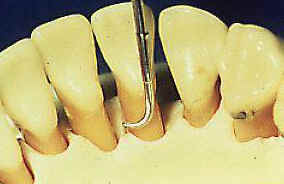

Observe

en la foto inferior la correcta ubicación de la hoja de la

cureta en la superficie dental.

| La

hoja de una cureta Gracey se encuentra correctamente aplicada cuando el

filo inferior se apoya contra el diente y el vástago terminal está

paralelo a la superficie dental que se desea limpiar. Aplique una presión

lateral contra el diente (raíz) y empuje hacia arriba, manteniendo el vástago

paralelo al eje mayor del diente o superficie de la raíz. (ver gráfico

derecha) |